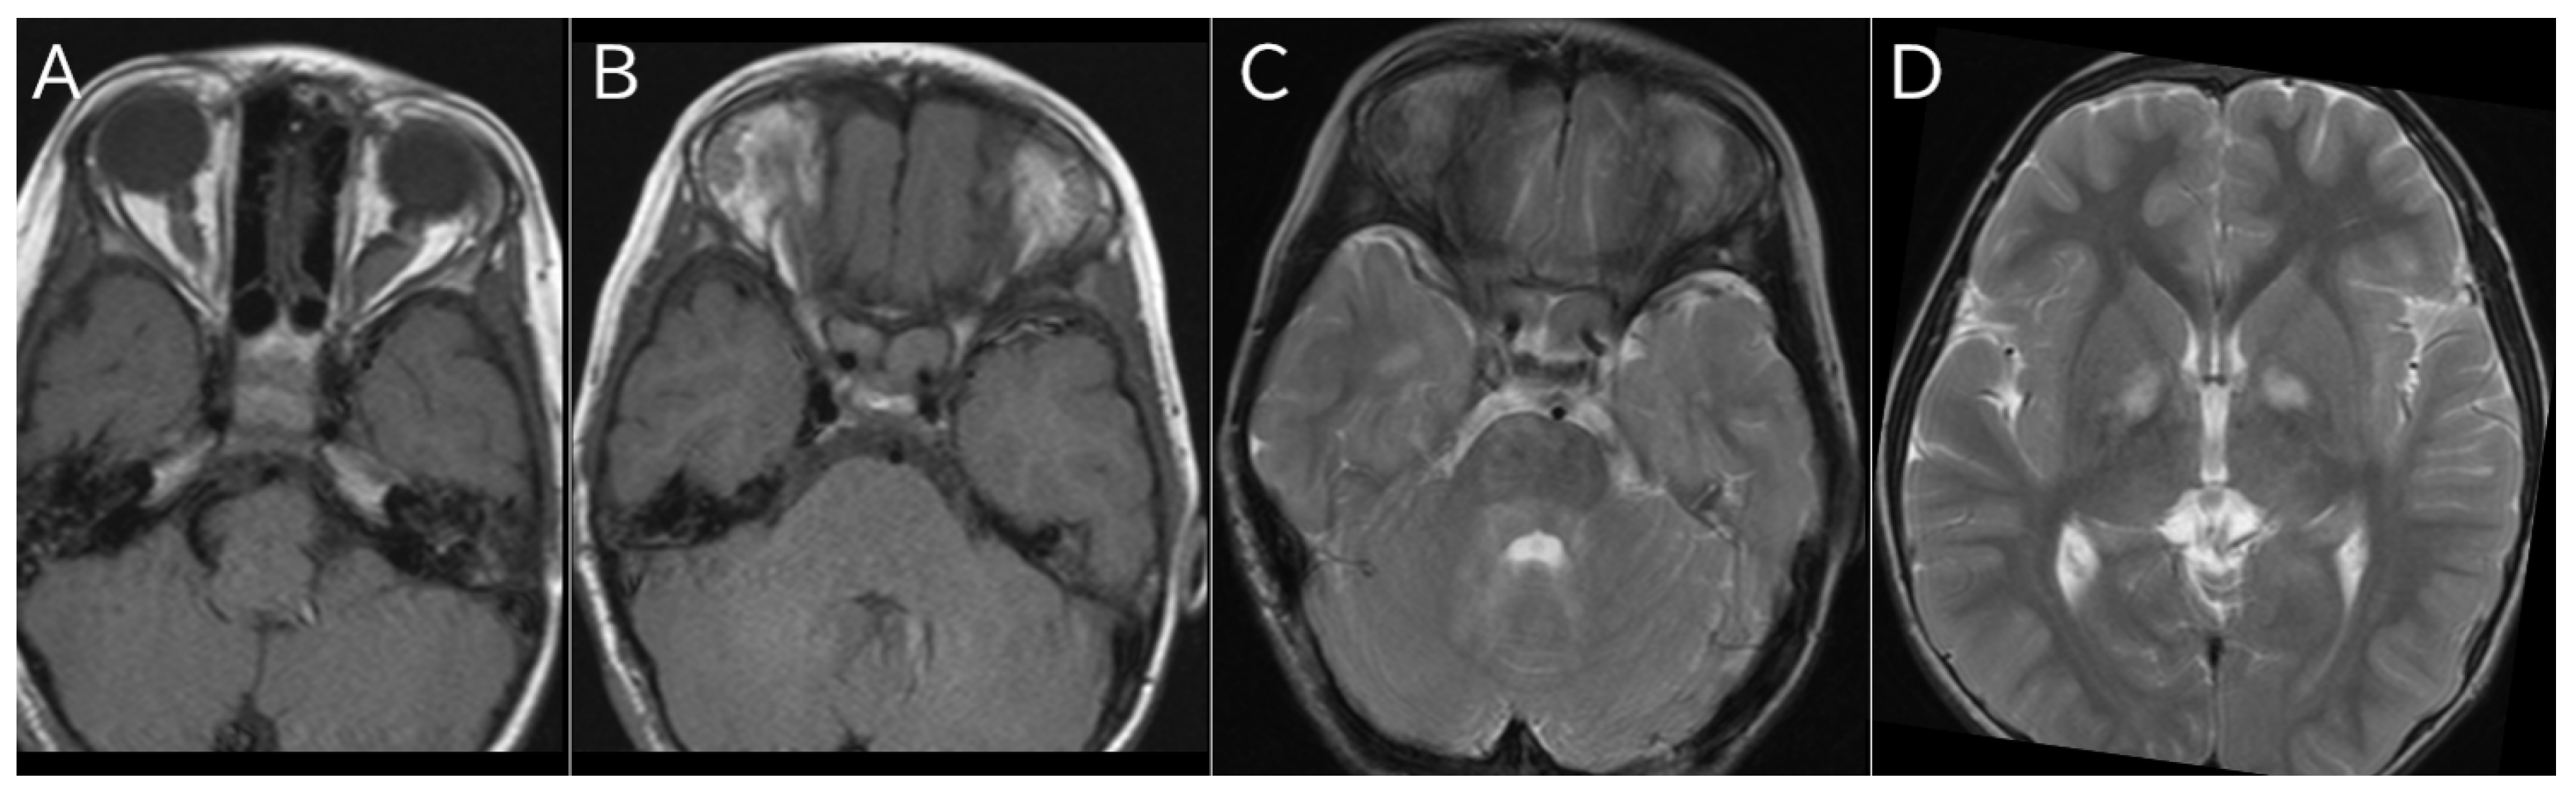

A typical MRI image of NF1 is shown (Figure 2).

Figure 2. MRI imaging findings of NF1. A/B: Bilateral optic gliomas in a 4-year-old girl; A: T1-weighted image; B: T2-weighted image. C: T2-weighted images of UBO in bilateral cerebellum of a 4-year-old girl. D: T2-weighted image of UBO in bilateral globus pallidus in a 7-year-old boy.